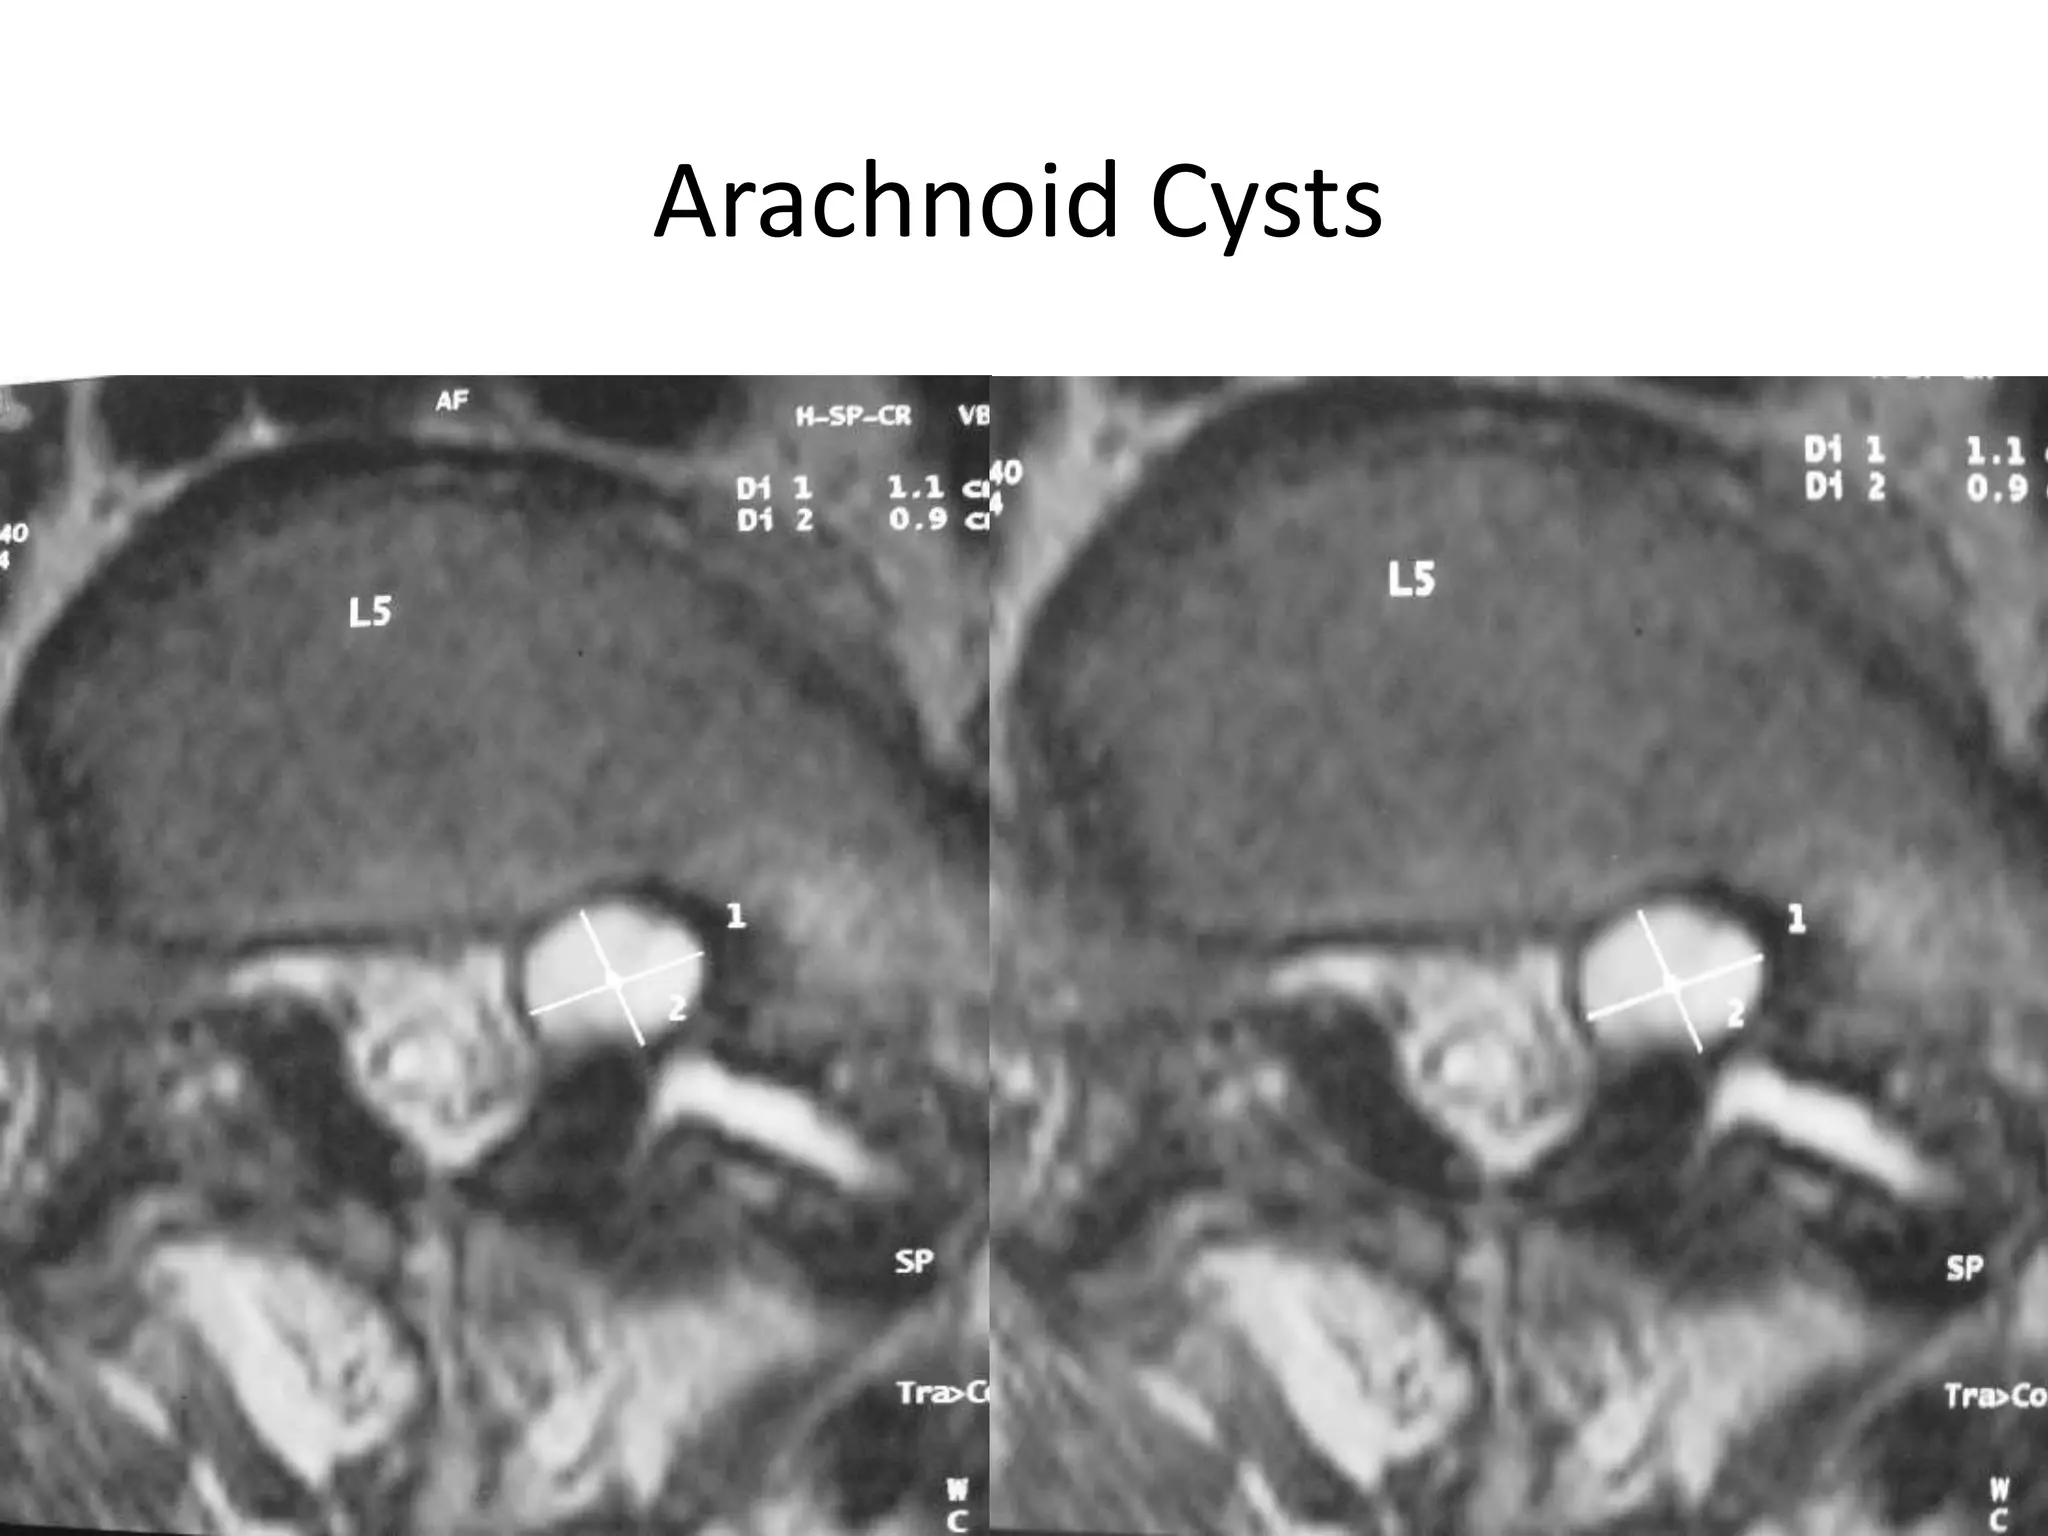

Arachnoid Cysts